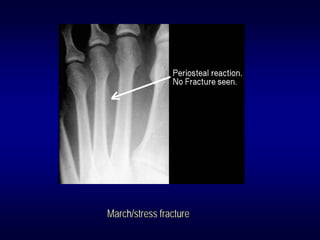

• Stress fractures

March/stress fracture